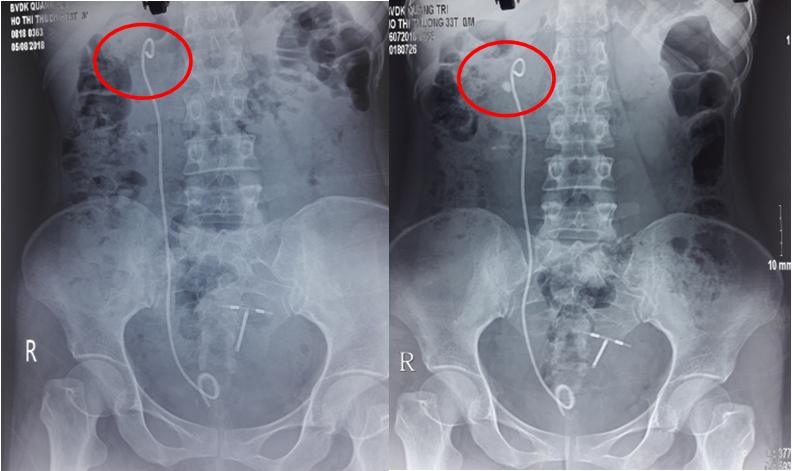

7

Hình 7.Sỏi thận trái trên bệnh nhân bị dị tật cột sống chia đôi

Tắc nghẽn đường tống sỏi cũng có thể là một chống chỉ định (tạm thời) đòi hỏi phải điều trị trước khi can thiệp bằng TSNCT. Những tắc nghẽn bao gồm xơ hẹp cổ đài, túi thừa đài thận (hình 5), hẹp khúc nối bể thận niệu quản, hẹp niệu quản, tăng sinh lành tính tuyến tiền liệt, hẹp niệu đạo hay hẹp miệng sáo.

8

Hình 8.Sỏi cực trên thận phải trong túi thừa đài thận

A, Phim KUB             B, Phim UIV